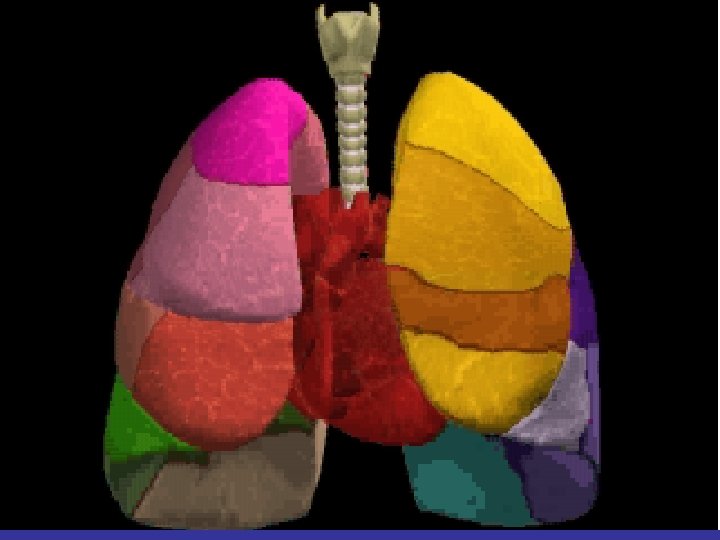

Lobes and Fissures